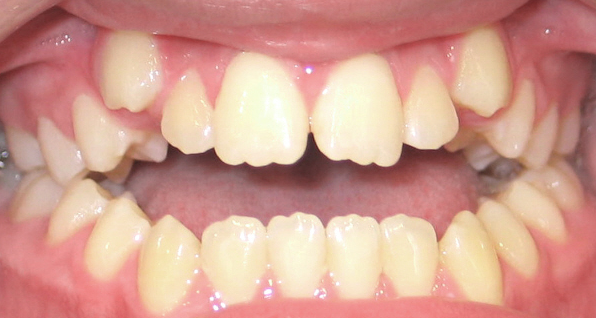

Open Bite

An open bite occurs when there is insufficient vertical overlap of the teeth. It is caused by oral habits such as a tongue thrust, thumb or finger sucking or when the jaws don’t grow evenly. Timing of treatment is critical to the overall success of the therapy.

How can an open bite be orthodontically corrected?

An open bite can be corrected through growth modification of the jaws using braces, extrusion of the anterior teeth and in some cases surgical correction of the jaws. Also breaking oral habits, such as digit sucking, will facilitate the correction of an open bite.

Before and After Photos: Open Bite Correction